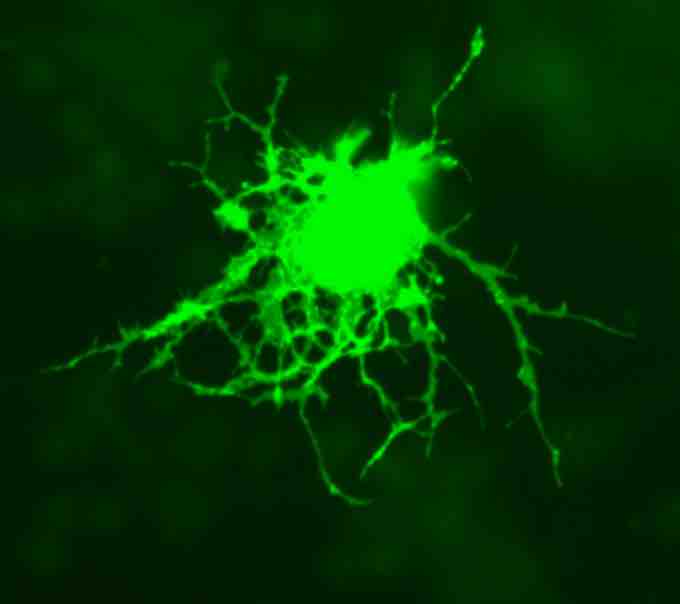

Astrocytes are star shaped delicate branching glial cells. Their numerous radiating processes cling to neurons and their synaptic endings. These astrocytes cover nearly all the capillaries in the CNS. They support and brace the neurons and anchor them to their nutrient supply lines. They also play an important role in making exchanges between capillaries and neurons. They also regulate the external chemical environment of neurons by removing excess ions and recycling neurotransmitters released during synaptic transmission.